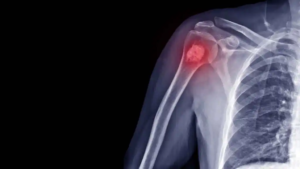

El sarcoma es un tumor poco frecuente que puede originarse en los tejidos de huesos, cartílagos, músculos, vasos sanguíneos y en los tejidos nerviosos, adiposos y fibrosos.

El sarcoma puede aparecer como como una tumoración en los brazos, piernas, tronco, cabeza y cuello o detectarse por estudios de imágenes.

- Sarcomas óseos o del esqueleto: se origina en el hueso, clasificado de la siguiente manera: osteosarcoma (tejido óseo), condrosarcoma (cartílago) y fibrosarcoma (componente fibroso de los huesos).